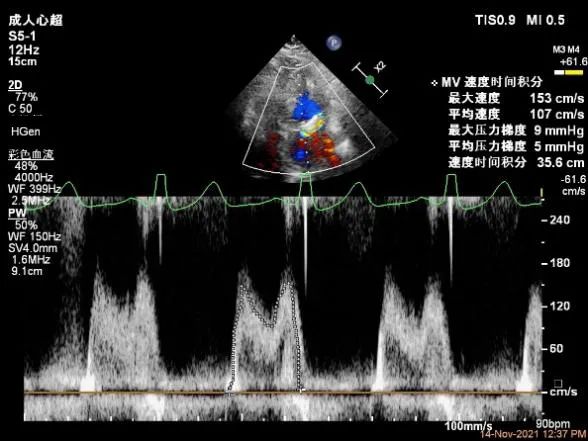

Bicom:MR(重度),反流束宽9.6mm,反流面积15.7cm²

PISA法定量EROA:1.05cm²,Rvol:148ml,RF:58%。

肺静脉血流频谱呈收缩期反向

二尖瓣口平均跨瓣压差:6mmHg